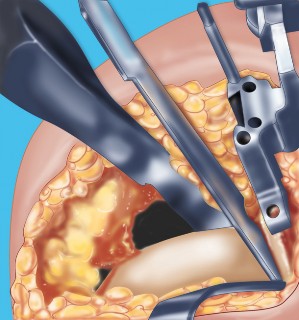

2. الوضع الجراحي والتعرض

- الوضع: يُوضع المريض في وضع الاستلقاء (Supine positioning) مع وضع كيس رمل أسفل الركبة أو حامل للساق يسمح بثني وفرد الركبة. يجب أن يكون الوضع مماثلاً لوضع جراحة TKA، مع استعداد لتحويل الإجراء إلى TKA إذا لزم الأمر.

- العاصبة (Tourniquet): تُستخدم عاصبة وتُوضع في أعلى الفخذ لتقليل النزيف.

-

الشق الجراحي:

يُستخدم شق طولي في الجانب الإنسي (الداخلي) من الركبة. يجب أن يكون الشق كبيرًا بما يكفي لتوفير رؤية جيدة للمفصل الرضفي الفخذي وإمكانية التحويل إلى TKA.

- فتح المفصل (Arthrotomy): يكون الفتح خطيًا وموازياً لألياف الوتر الرضفي، ويمتد إلى عظم الظنبوب وإلى الجزء السفلي من الرضفة.

- تحرير الأنسجة الرخوة: يتم قطع الغضروف الهلالي لتحرير الأنسجة الرخوة من عظم الظنبوب، ويتم تطوير سديلة تحت السمحاق في نمط دائري حول الظنبوب. يُمدد هذا التحرير خلفيًا لضمان توازن الأربطة.

-

تصحيح التشوه:

الهدف هو تحقيق تصحيح طفيف للتشوه، مع وجود رخاوة كاذبة طفيفة عند تطبيق ضغط تفحجي في نهاية الإجراء. يجب تجنب التصحيح المفرط.